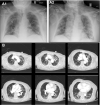

In this article, the authors review manifestations of COVID-19 in older adults, normal physiologic changes and frequent comorbidities of aging that increase pathogenicity, factors contributing to overwhelming viral spread among seniors, negative effects on health and well-being resulting from measures to control the virus, and health-system improvements necessary to protect and care for this vulnerable population.